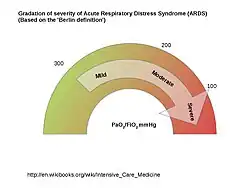

*Need objective assessment (ex.Echocardiography) to exclude hydrostatic oedema if no risk factor present.†Mild >200≤300mmHg, Moderate >100≤200mmHg, Severe ≤100mmHg [Fig 1]. If the altitude is higher than 1000m (from Mean Sea Level), a Correction factor should be calculated as follows:[PaO2/FiO2X(Barometric Pressure/760)].^This may be delivered non-invasively in Mild acute respiratory distress group.PaO2Arterial Oxygen tension; FiO2Fractional Inspired Oxygen Concentration; CPAP Continuous Positive Airway Pressure; PEEP Positive End-Expiratory Pressure. [1]